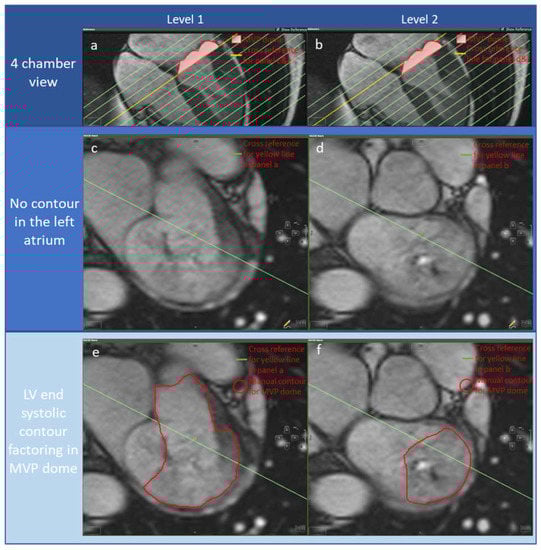

| AI-derived without including MVP doming volume in LVESV | |

| LV end-diastolic volume (mL) | 200 ± 66 |

| LV end-systolic volume (mL) | 77 ± 33 |

| LV stroke volume (mL) | 123 ± 48 |

| LV ejection fraction (%) | 61 ± 14 |

| MV ejection fraction (%) | 11 ±11 |

| Manually refined including MVP doming volume in LVESV | |

| LV end-diastolic volume (mL) | 202 ± 63 |

| LV end-systolic volume (mL) | 98 ± 37 |

| LV stroke volume (mL) | 105 ± 38 |

| LV ejection fraction (%) | 52 ± 11 |

| MV ejection fraction (%) | 13 ± 12 |